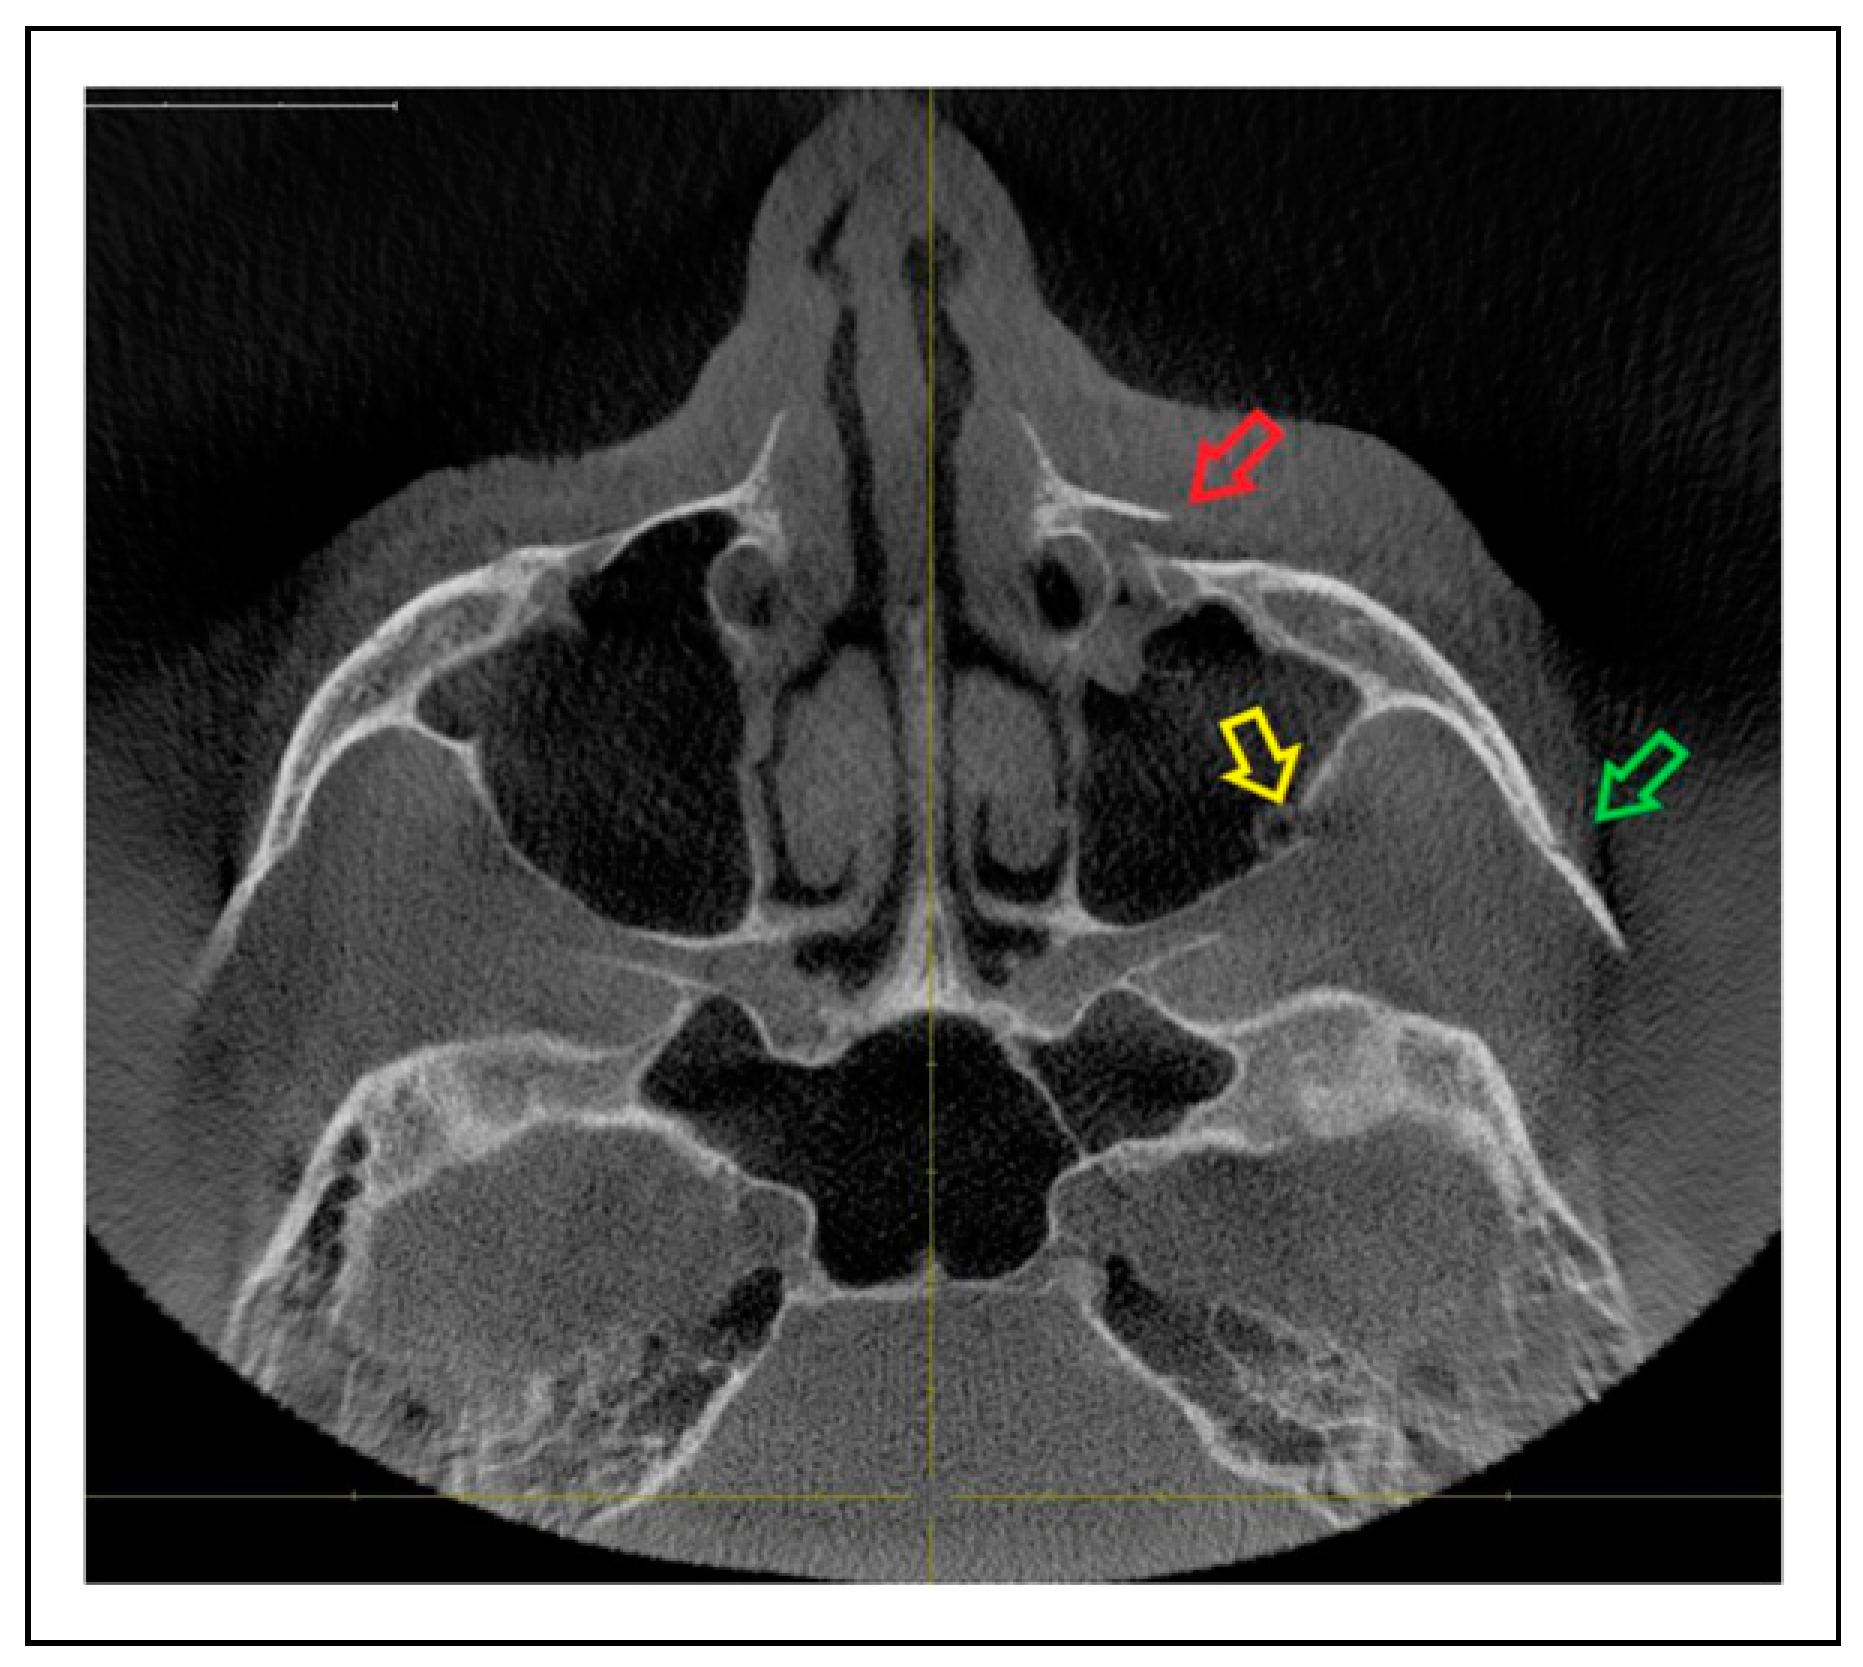

- Fracture location according to the anatomic sutures of the zygoma

- Radiologic involvement of maxillary sinus wall and paranasal buttress fractures.

- Zygomaticosphenoidal suture (ZS)—the anterolateral orbital floor

- Trisutural fracture with the following fracture line combinations:

- ZM suture + ZF suture + ZS suture

- IOR + ZF suture + ZS suture

Patterns of ZMO Fractures Regarding the Anatomic Sutures of the Zygoma

Fracture Prevalence of Maxillary Sinus Wall and Paranasal Buttress as Concomitance to the ZMO